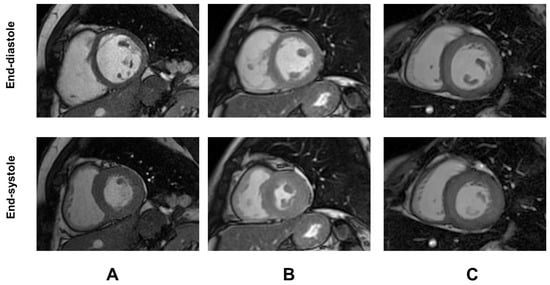

Demographic and clinical characteristics and MRI findings of TDT patients are summarized in Table 1. Representative examples of GTI are shown in Figure 1.

Figure 1.

Representative examples of global wall thickness index (GTI) in three female patients with TDT. (A) Patient with normal GTI. (B) Patient with increased GTI but normal LV mass index [concentric remodeling]. (C) Patient with both increased GTI and LV mass index [concentric hypertrophy].